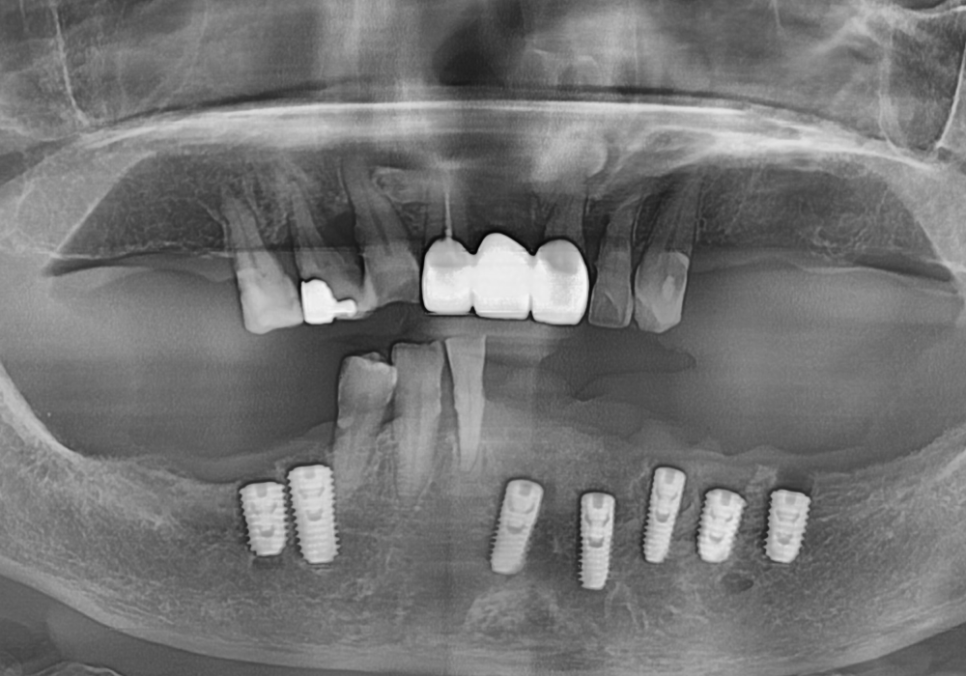

계획했던 위치와 깊이에 맞춰 임플란트 7개가

안정적으로 자리를 잡았습니다.

231103

심어야 할 개수가 많고 잇몸뼈 상태도

좋지 않은 어려운 조건이었지만,

가이드 덕분에 이미 정해진 위치에

오차 없이 신속하게 마무리할 수 있었습니다.

임플란트가 뼈와 단단히 붙은 것을

확인한 뒤에는 마지막 치아 모양을

만드는 과정을 진행했어요.